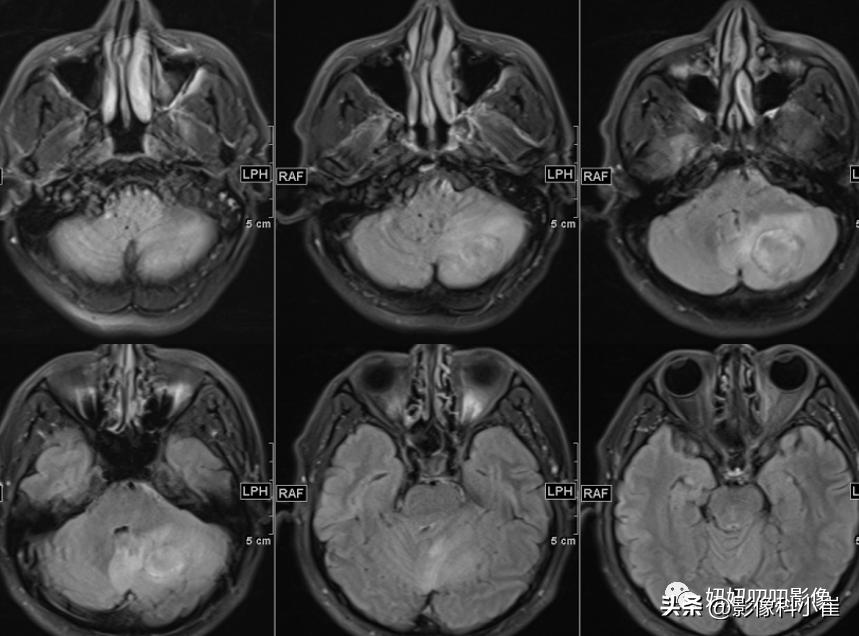

左侧小脑半球片状长短T1等长T2 异常信号,边界不清,大小约3.2X2.9X2.4cm,T2-Flair呈等高信号,周围见斑片状水肿带,DWI 示病变明显弥散受限,增强扫描可见不均匀环状强化。双侧放射冠、皮层下另见少许斑点状等长 T1、长T2 异常信号灶,T2 Flair 呈高信号,DWI未见明显弥散受限,增强扫描未见明显异常强化。第四脑室受压变窄,幕上脑室系统未见明显扩张。脑沟、脑裂略增宽。中线结构无移位。双侧筛窦、上领窦粘膜增厚。

这个病有意思,周边T2黑黑的,弥散受限这么明显,强化还是环形强化,从环形强化入手?转移,胶质母,脓肿。从弥散收入,淋巴瘤,脓肿,胶质母,T1还有出血,信号不均匀,边界清楚。其实看到出血觉得是胶质母,其实看看弥散的均匀度,和环状强化的边,并不是那么花环样子,加上白细胞高,可能还是脓肿。